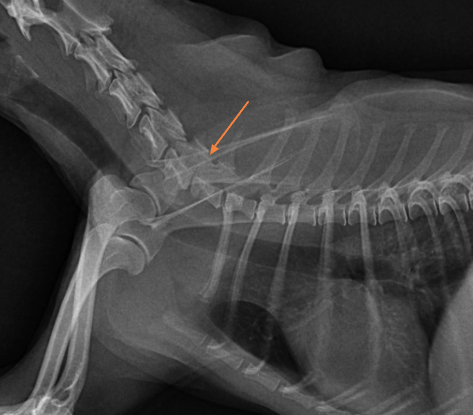

(6월초 입니다 우측 하단 화살표 클릭시 사진 커집니다)

공격적인 치료가 필요한 수준의 이상 상태는 아닌것으로 판단되니 환자를 직접 본 주치의의 판단을 따르시기 바랍니다. 또한 아래 사진처럼 경추 디스크 가능성이 있으니 이 부분에 대해서도 상담 받으시기 바랍니다.